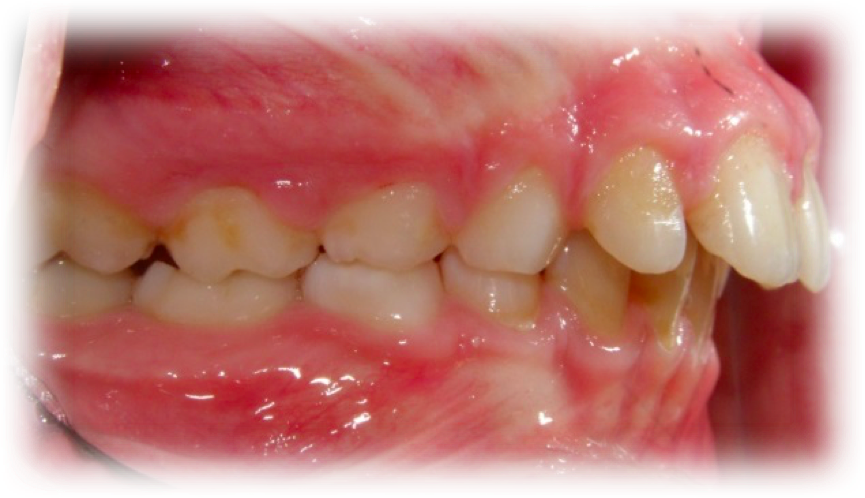

Överbett betyder att överkäkens framtänder biter långt framför underkäks framtänderna.

Stort överbett är en vanlig bettavvikelse som förekommer hos cirka 20 procent av den unga befolkningen. Överbett större än 6 mm har i skandinaviska material visat sig förekomma hos cirka 15 procent av tioåriga barn.